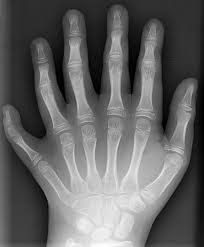

Malformaciones congénitas, sindactilia, polidactileas,macrodactileas,Lima Peru, cirugiademanoperu, Dr. Ugarte

Polidactilea Sindactileas

Macrodactileas Sindrome anillo constrictor